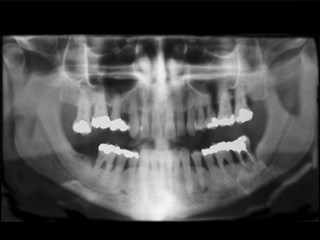

Röntgenbilderna kan exempelvis avslöja karies, tandsten, tandlossning, infektioner, sjukliga förändringar, felställda tänder. Här avslöjar röntgenbilden allvarlig tandlossning.

Röntgen

Röntgen hjälper tandläkaren att se mer. Röntgenbilderna kan bland annat avslöja karies, tandsten, tandlossning, infektioner, sjukliga förändringar, felställda tänder som annars inte upptäckts i tid.